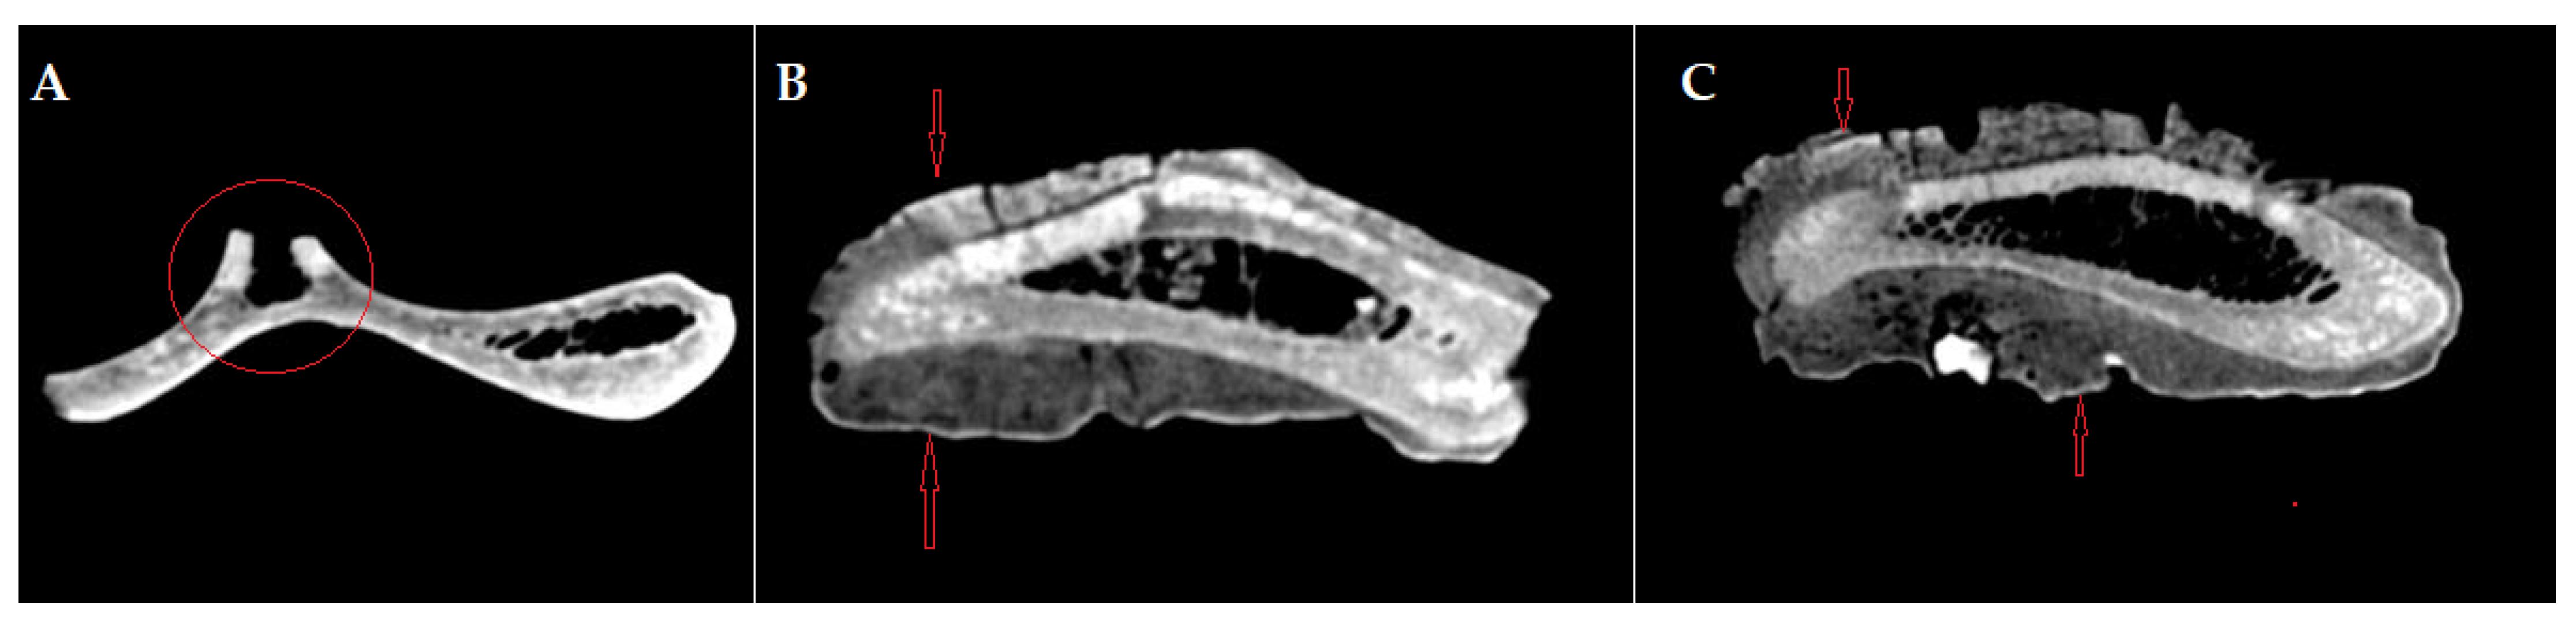

The gross features (Figure 1) detected in the distal portion of the scapula (neck of the scapula) include a major hypertrophy of the region due to the formation of an exuberant osseous tissue.

The newly formed bone tissue displays an irregular surface just dorsally (2–3 mm) to the glenoid cavity (Figure 1), all around the neck of the scapula. Consequently, the infraglenoid tubercle and the coracoid process are barely visible, being embedded in the osteophytes/exostoses situated in the neck of the scapula. The osteophytes and exostoses are most likely of cancellous bone, a fact suggested by the X-ray images (Figure 2).

Figure 1. The scapular fragment. The aspect of the lesion onto the lateral surface of the scapular neck. Note the development of osseous tissue and the marking of the suprascapular artery and nerve trajectory (arrow).

Figure 3. CT images of the scapula: (A) axial section of the scapula, preserving the base of the dorsal spine on the cranial edge—red circle; (B,C) axial section of the scapula in the neck region of the scapula, intercepting the proliferated bone on both sides, lateral and medial—red arrows.